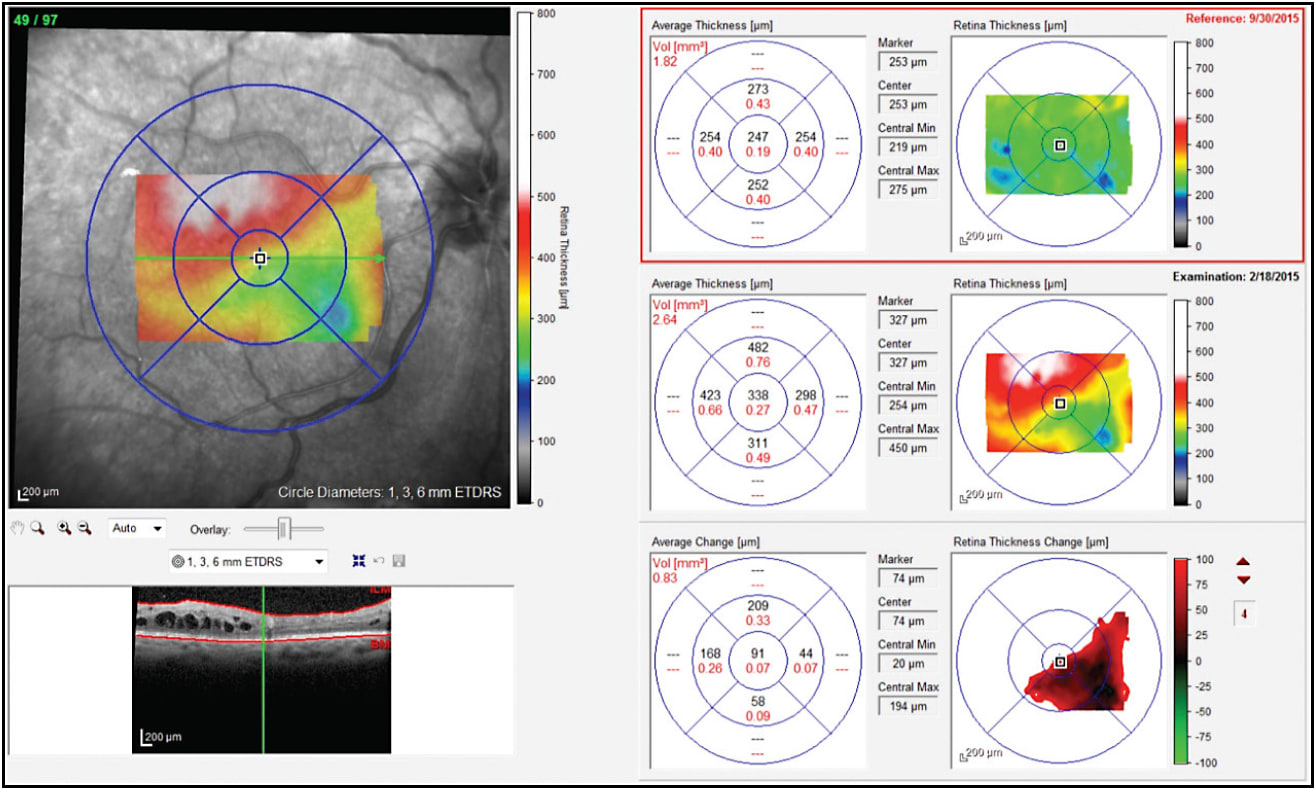

On June 1, 2015, Iluvien was implanted in the patient’s left eye for the same reasons it was used in the right eye: limited response to anti-VEGF therapy, a good response to corticosteroids, and recurrent DME requiring repeat injections. According to the previous OCT, which was obtained on May 18, 2015, CRT was 368 µm and VA was 20/32 (Figure 4).

One month after the patient received Iluvien OS, July 1, 2015, CRT improved to 261 µm and VA improved to 20/25. Throughout the nine subsequent months, with no additional treatment, CRT and VA remained consistent (Figure 5) and the highest IOP recorded was 16 mmHg. The one Iluvien treatment the patient received in that span of a year was far less of a burden than the frequent treatments she had been undergoing.